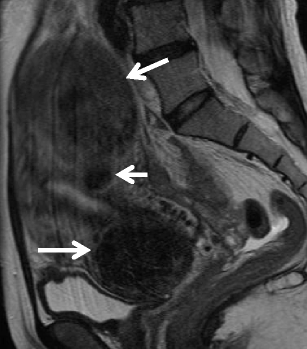

Benign uterine leiomyomas may show unusual growth pattern that should not be mistaken for malignancy [42, 44]. Leiomyomas may show extensive venous extension, which is known as intravenous leiomyomatosis. Subserosal uterine leiomyoma extending into the broad ligament or the retroperitoneum also may produce infiltrative appearance. Rarely, submucosal myomas can be pedunculated and prolapse into the cervical canal or vagina [45].

A huge subserosal leiomyoma in a 40-year-old woman. a Sagittal T2-weighted image demonstrates a huge heterogenous tumor consisting of cystic components of bright intensity anteriorly (arrows) and solid component of intermediate to low intensity. Note the tumor vessels extending from the myometrium to the tumor (arrowhead)